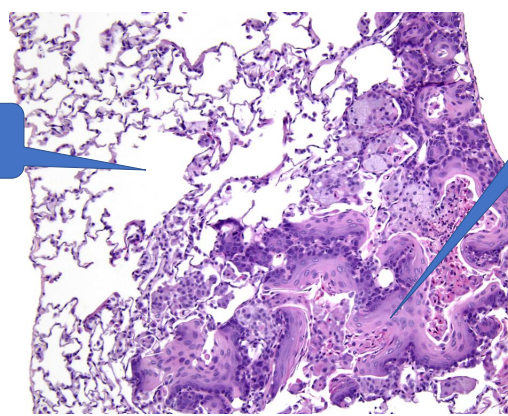

1- normal alveoli

2- Squamous metaplasia

Normal alveoli epithelium replaced by squamous epithelim which cant help gas exchange

Vitamin A deficiency

1- squamous metaplasia

pseudostratified ciliated columnar —> squamous

loss of infection:

1- Loss of cilia: Without cilia, the epithelium can no longer sweep mucus and trapped microbes out of the airway.

2- Impaired mucociliary clearance: Goblet cell function is disrupted, so mucus isn’t produced or moved properly. Mucus and debris accumulate, allowing pathogens to multiply and cause infection.